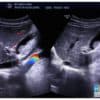

– Chỉ khoảng 15-20% sỏi mật có tính cản quang và có thể nhìn thấy trên phim X-quang. => Case lâm sàng 1: => Case lâm sàng 2: – Siêu âm có độ nhạy và độ đặc hiệu cao (95%) đối với sỏi >2 mm. – Khi sỏi tập trung thành đám nằm sát nhau hoặc sỏi quá lớn thì không thấy toàn bộ hình viên sỏi mà chỉ thấy một vòng cung tăng âm kèm bóng cản => Videos sỏi lấp đầy túi mật: – Doppler màu: có thể hiển thị hiện tượng “twinkling artifact” và đặc biệt hữu ích trong việc xác định các viên sỏi nhỏ. – Một số hình thái đặc biệt: + Một số sỏi nhỏ ở phễu túi mật hoặc ở cổ túi mật thường bị che khuất bởi hơi tá tràng có thể bỏ qua. + Sỏi trôi nổi trong dịch mật: trường hợp dịch mật đặc – Khối tăng âm nhưng không kèm bóng cản, mức độ âm ít hơn sỏi. => Case lâm sàng 0: => Case lâm sàng 1: => Case lâm sàng 2: => Case lâm sàng 3: => Case lâm sàng 4: => Case lâm sàng 5: => Case lâm sàng 6: => Case lâm sàng 7: – Thường thấy ở các bệnh nhân nhịn đói kéo dài, tắc đường mật ngoài gan và bệnh hồng cầu hình liềm hoặc các nguyên nhân tan máu khác. Có thể tự mất đi và xuất hiện lại sau vài tháng, nó có thể là bước trung gian để tạo sỏi mật. => Case lâm sàng 1: => Case lâm sàng 2: sỏi + bùn mật – Túi mật bị lấp đầy bùn mật có thể đồng âm với gan (gan hóa túi mật trên siêu âm). => Case lâm sàng 1: => Case lâm sàng 2: => Case lâm sàng 3: => Case lâm sàng 4: => Case lâm sàng 5: – Phân biệt bùn mật: chảy máu hoặc mủ đường mật hoặc các mảnh viêm. Bùn kết tụ có thể biểu hiện dưới dạng một khối tăng âm, di động, không bóng cản hoặc một khối tăng âm không bóng cản dạng polyp ở phần thấp của túi mật. Bùn mật kết tụ giả khối u thường di động chậm khi thay đổi tư thế bệnh nhân, nhưng nó có thể không di động. Chảy máu túi mật tạo khối đồng nhất hoặc không do giai đoạn thoái triển khác nhau của khối máu tụ, có thể kèm vách tăng âm. => Case lâm sàng 1: => Case lâm sàng 2: => Case lâm sàng 3: – Nhiều loại sỏi trên cùng một bệnh nhân. – Chẩn đoán sỏi túi mật chỉ cẩn dựa vào siêu âm là đủ. CLVT thường được chỉ định trong những trường hợp siêu âm gặp khó khăn: – Nhạy và đặc hiệu hơn CT trong việc phát hiện sỏi nhỏ, sỏi không cản quang (sỏi bùn). – Chuỗi xung đường mật MRCP hiện nay được sử dụng phổ biến trong chẩn đoán bệnh lý gan mật: nốt trống tín hiệu khu trú trong túi mật. => Case lâm sàng 1: => Case lâm sàng 2: => Case lâm sàng 3: – Tạo hình ảnh mức dịch-dịch. – Hội chứng Mirizzi là một biến chứng của sỏi túi mật, xảy ra khi có hiện tượng tắc nghẽn của ống gan chung bởi sỏi kẹt ở ống túi mật hoặc túi Hartmann. – Phân loại: – Đặc điểm hình ảnh: => Case lâm sàng 1: => Case lâm sàng 2: => Case lâm sàng 3: => Case lâm sàng 4: => Case lâm sàng 5: => Case lâm sàng 6: – Liên tục với thành túi mật, bờ đều, không có bóng cản, không di động khi thay đổi tư thế. – Hình ảnh tăng âm dạng đường ray, không bóng cản. – Do u phát triển lấp đầy lòng túi mật, không còn dịch mật bên trong, xóa mất thành túi mật, có thể lan tràn ra xung quanh và thường lan đến các ống mật gây tắc nghẽn. – Dày lan tỏa hoặc khu trú thành túi mật do u thâm nhiễm dọc theo thành túi mật (dày > 1cm), hồi âm tăng hoặc giảm. – Khối nhú lên trong lòng túi mật, hình ảnh dạng nấm, kích thước > 1cm – Túi mật sứ (Porcelain Gallbaladder) là dạng hiếm gặp của viêm túi mật mạn với biểu hiện vôi hóa thành túi mật hoàn toàn hoặc rải rác. => Case lâm sàng 1: => Case lâm sàng 2: – Đặc điểm siêu âm: => Case lâm sàng 1: => Case lâm sàng 2: – Cholesterolosis là hậu quả của lắng đọng cholesterol ester trong các đại thực bào dưới niêm mạc. – Máu có thể xuất hiện dưới dạng bùn tăng âm trong túi mật ở giai đoạn khởi đầu, và giai đoạn sau là một khối tăng âm hoặc giảm âm, di động, không bóng cảnII. Chẩn đoán x-quang

– Tính di động không phải lúc nào cũng được thể hiện rõ, do đó có thể gây nhầm lẫn với polyp hoặc ung thư túi mật.

– Không có mạch máu bên trong khi sử dụng Doppler màu.* Bùn mật